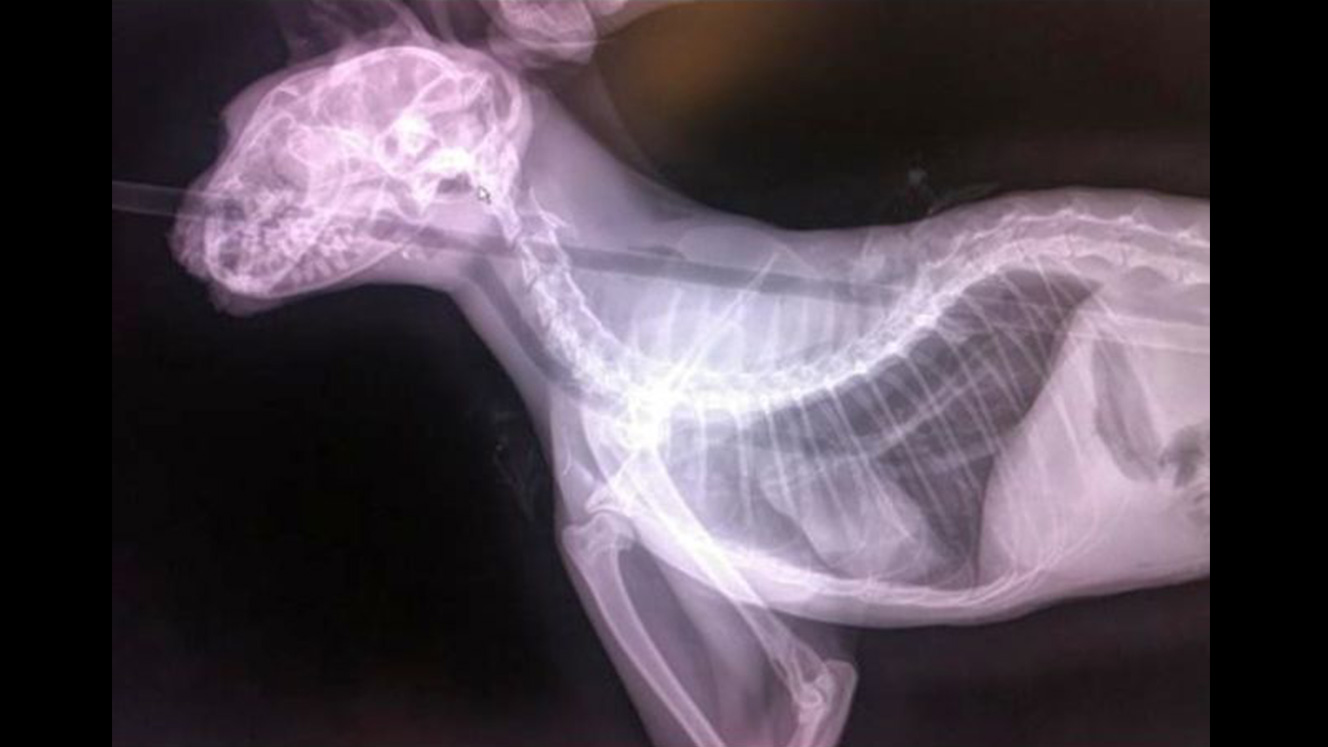

The feral cat was found Wednesday in Nisson Park, 30 S. 200 West, with an arrow through its mouth and protruding out of its back. A veterinarian was able to remove the arrow and the cat is recovering at Animal Welfare Services in Washington City.